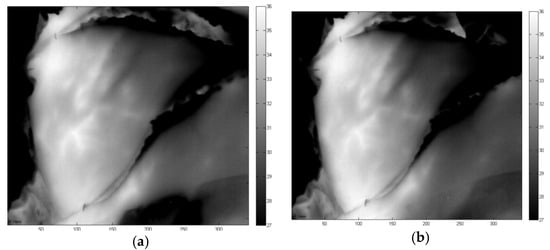

3.1. Left Flap in Rest 2 Perforators (A+B) Open